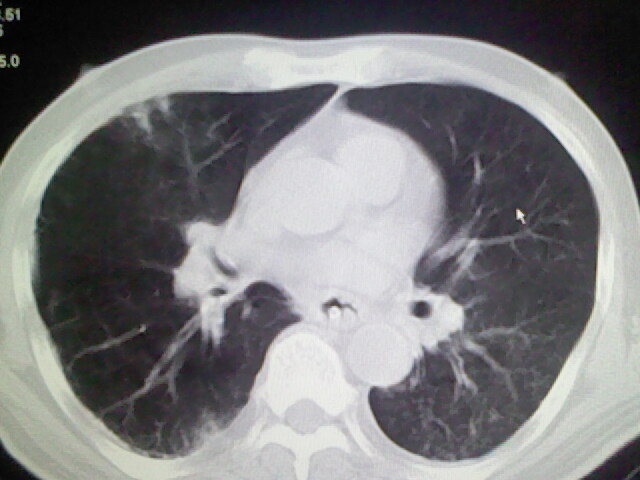

右侧肺部见片状密度增高影,边缘模糊。考虑炎症。另食管壁增厚。

右肺肺气肿并炎症。

肺气肿并炎症。

右肺上叶前段病呈楔形,其尖端指向肺门,考虑肺动脉栓塞可能性大.